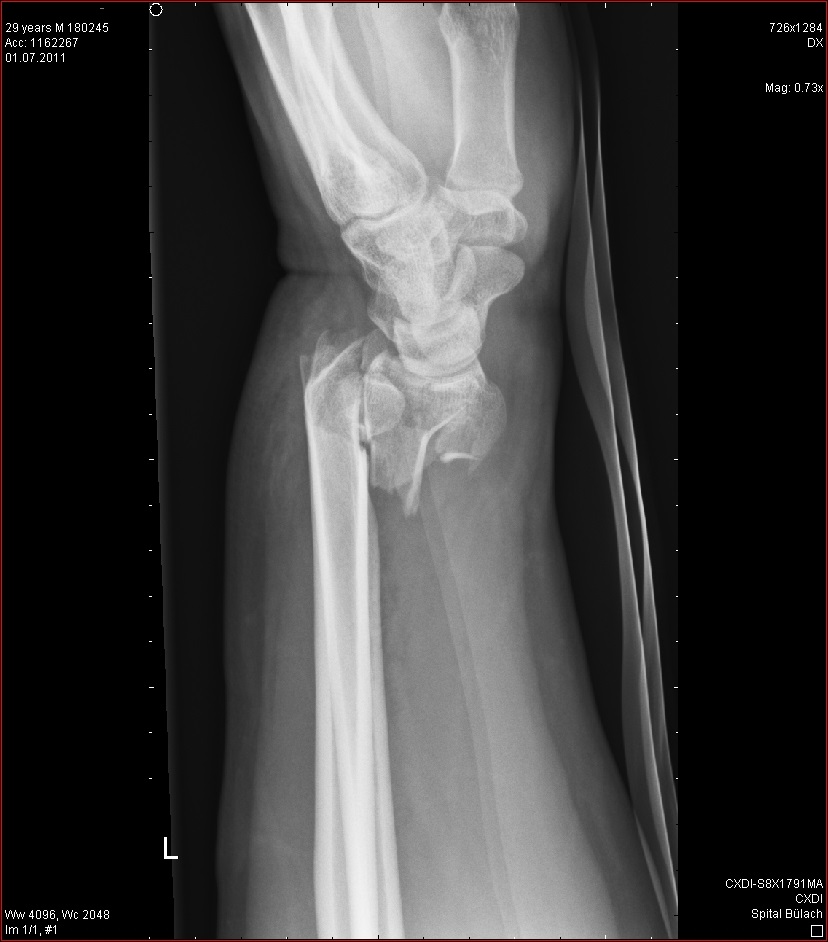

Die erste OP dann mit 18. Die zweite mit 22 und die letzte im Dezember 2013.